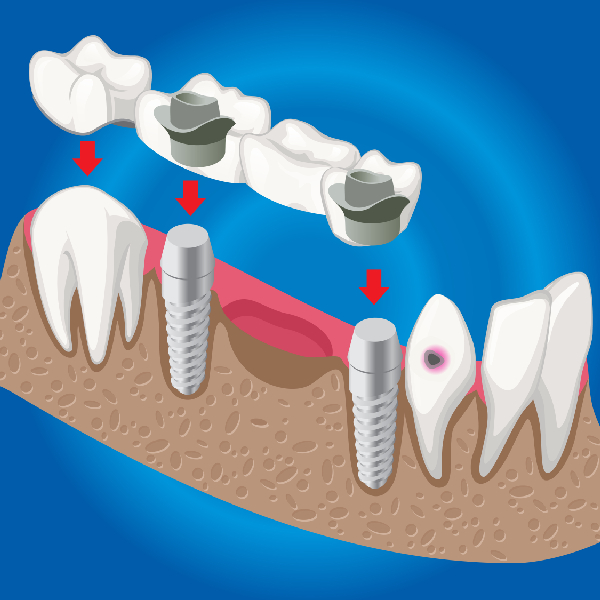

The Dental Implant Procedure

The dental implant process is a carefully scheduled and carried out procedure at Dr. Prakash Gupta's Dental Clinic. Below is a quick summary